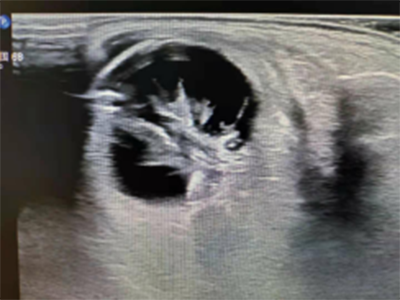

上圖是1例眼外傷患者眼內(nèi)機(jī)化膜形成,彩超檢查:膜狀回聲內(nèi)未檢測到血流信號